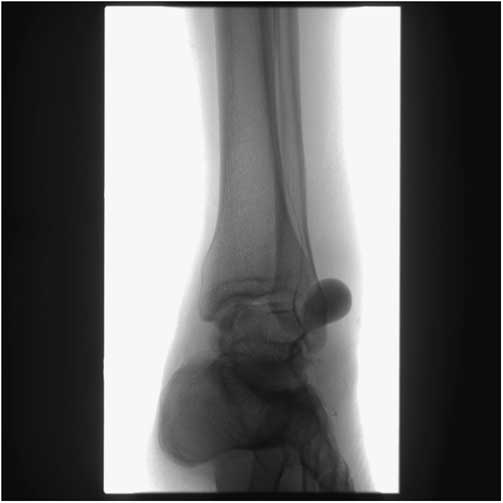

Initial ED management consisted of oral and parenteral analgesia with acetaminophen, ketorolac, and morphine, as well as intravenous ceftriaxone. X-rays revealed significant soft tissue swelling over and around the lateral malleolus, with a few well-corticated ossific densities in the swollen tissue. No fracture or air in the tissue was identified. Laboratory tests were unremarkable. The differential diagnosis included an expanding hematoma secondary to vascular injury, abscess, DVT, and complex regional pain syndrome.

Duplex ultrasound performed in the radiology suite the following morning (eighth day after initial injury) revealed a left anterior tibial artery pseudoaneurysm at the level of the ankle measuring 2.94×1.86 cm, with a 5.6×1.9 cm hematoma overlying the lateral ankle (Figures 2 and 3). Diagnostic ultrasound images of the lesion were obtained by scanning over skin marked with the large X (Figure 1), corresponding to the area of maximal swelling and pain. Distal flow was identified within the dorsalis pedis artery. The diagnosis was confirmed with CT angiography, which demonstrated a large pseudoaneurysm arising from the dorsal-lateral aspect of the proximal dorsalis pedis artery. Of note, after imaging the patient was re-examined and found to have an easily audible bruit in the area of the anterolateral ankle and dorsum of the foot, overlying the pseudoaneurysm.